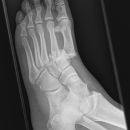

Lisfranc Luxationsfraktur